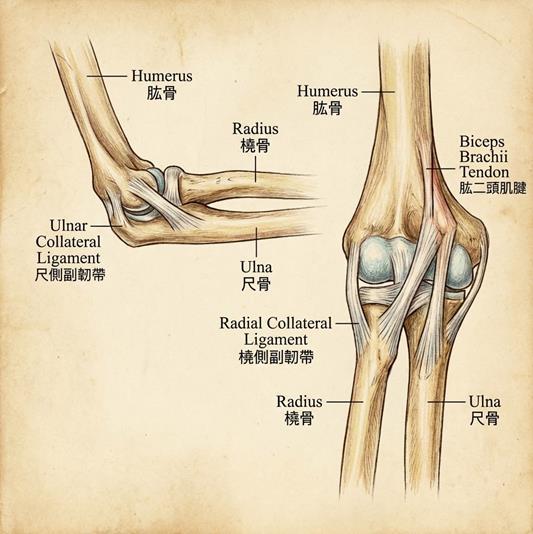

骨骼與肌肉互相配合,作

為槓桿支點,讓我們能跑

跳、彎腰與揮動雙手。